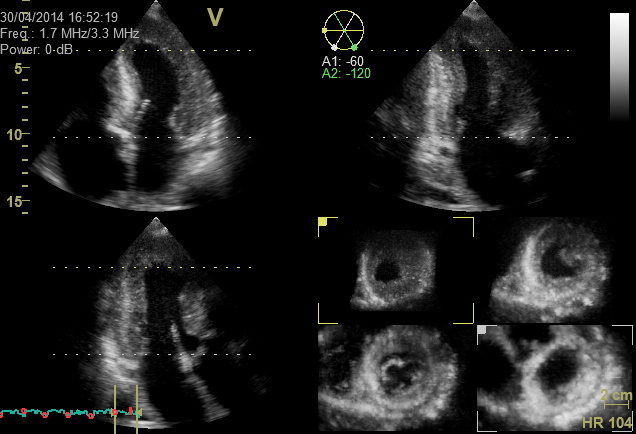

Die transthorakale dreidimensionale Echokardiographie (3D-TTE) liefert bei bestimmten Fragestellungen Zusatzinformationen zur transthorakalen zweidimensionalen Echokardiographie (2D-TTE).

Mit der transthorakalen 3D-Echokardiographie wird ein kompletter Volumendatensatz des gesamten Herzens aufgenommen, der eine räumliche Ansicht verschiedener Herzstrukturen erlaubt. Dadurch können z.B. Herzklappen räumlich so dargestellt werden, wie sie ein Herzchirurg im Rahmen einer Herzklappenoperation sieht. Nach einer MitraClip Implantation kann die Ausrichtung und Lage des Clips an der Mitralklappe gut dargestellt werden. Auch Messungen an der Hauptschlagader werden erleichtert, da eine genaue Ausrichtung der zu messenden Strukturen möglich ist. Es können zudem Informationen über die Herzmuskelmasse z.B. bei einem durch Bluthochdruck verdickten Herzmuskel („Hochdruckherz“) gewonnen werden.